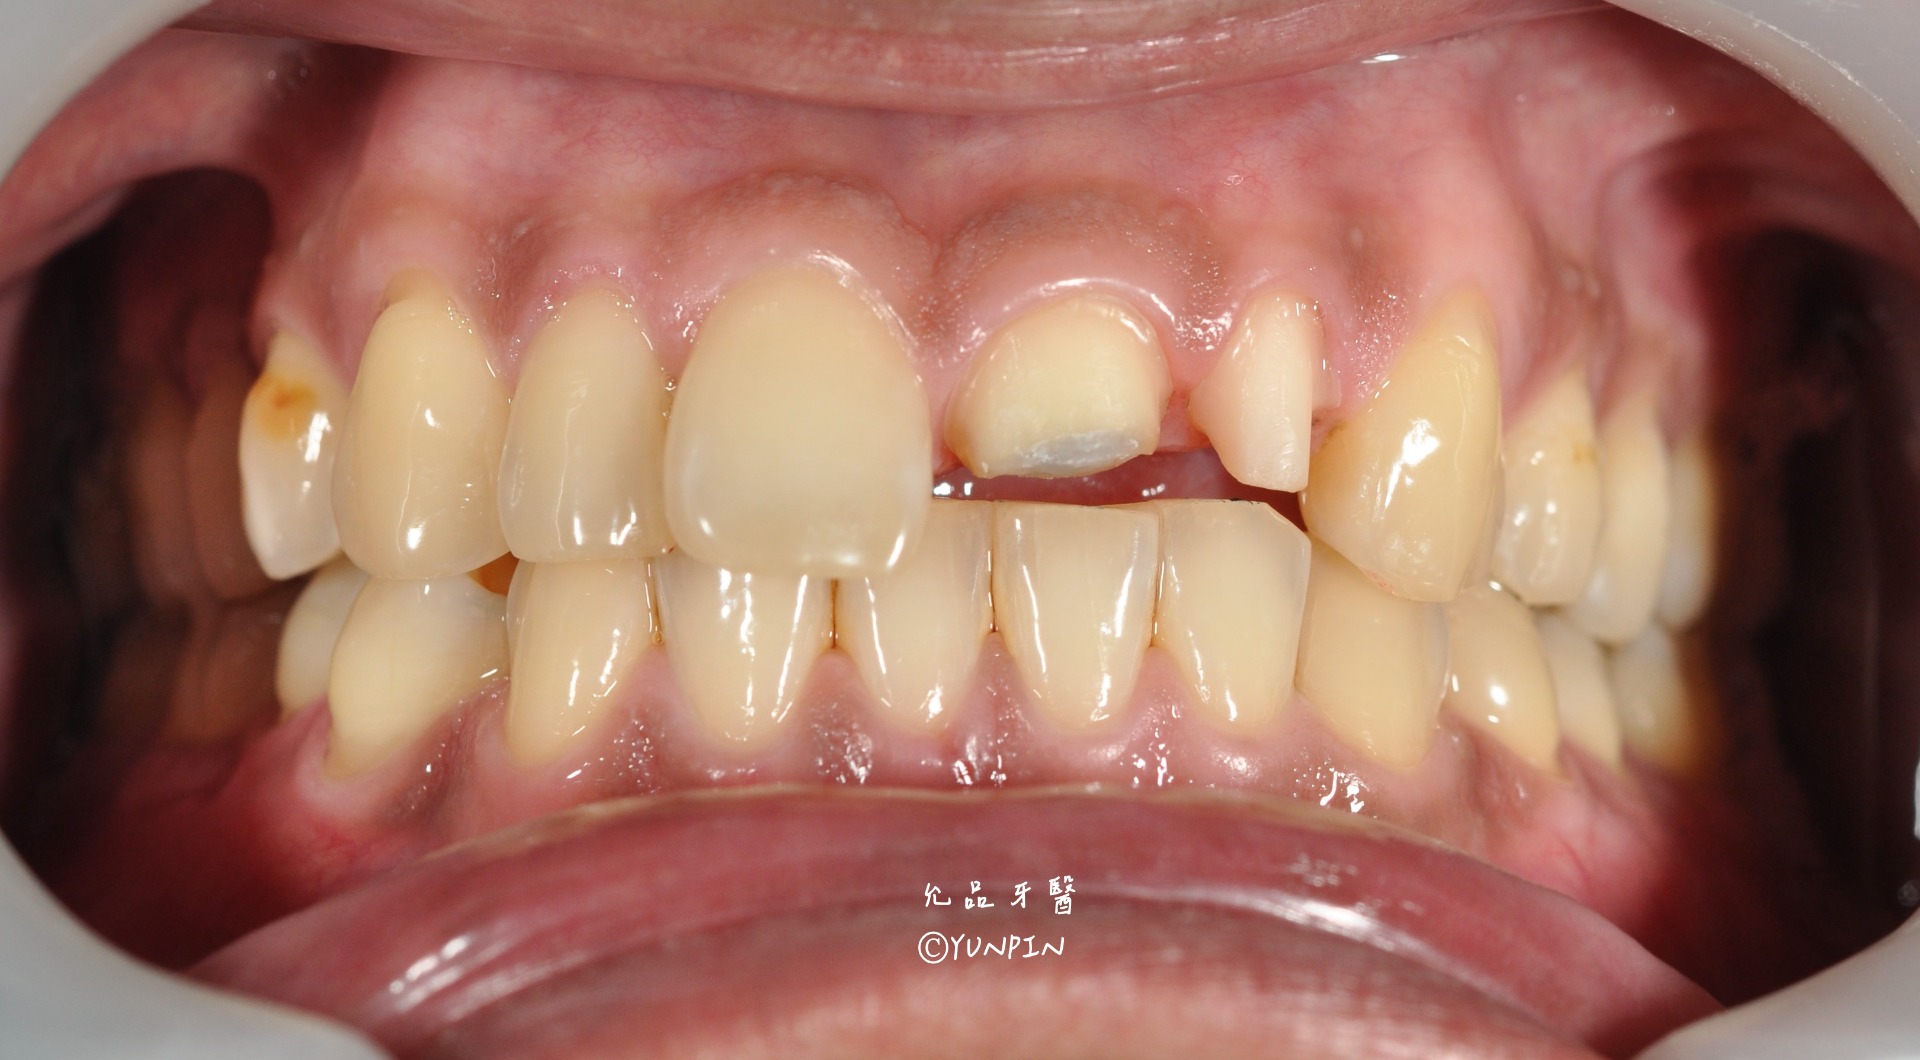

前牙假牙膺復案例

患者主訴跌倒撞斷左上正中門牙及側門牙,美觀上較不佳,

協助使用假牙完成前牙區斷牙重建。

口內實際狀況